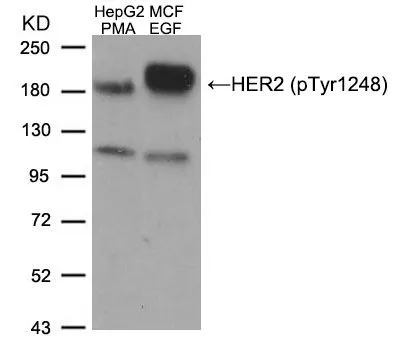

- Delivery Days Customer9

- Application Supplier NoteWB: 1:500-1:1000. ICC/IF: 1:100-1:200. IHC-P: 1:50-1:100. *Optimal dilutions/concentrations should be determined by the researcher.Not tested in other applications.